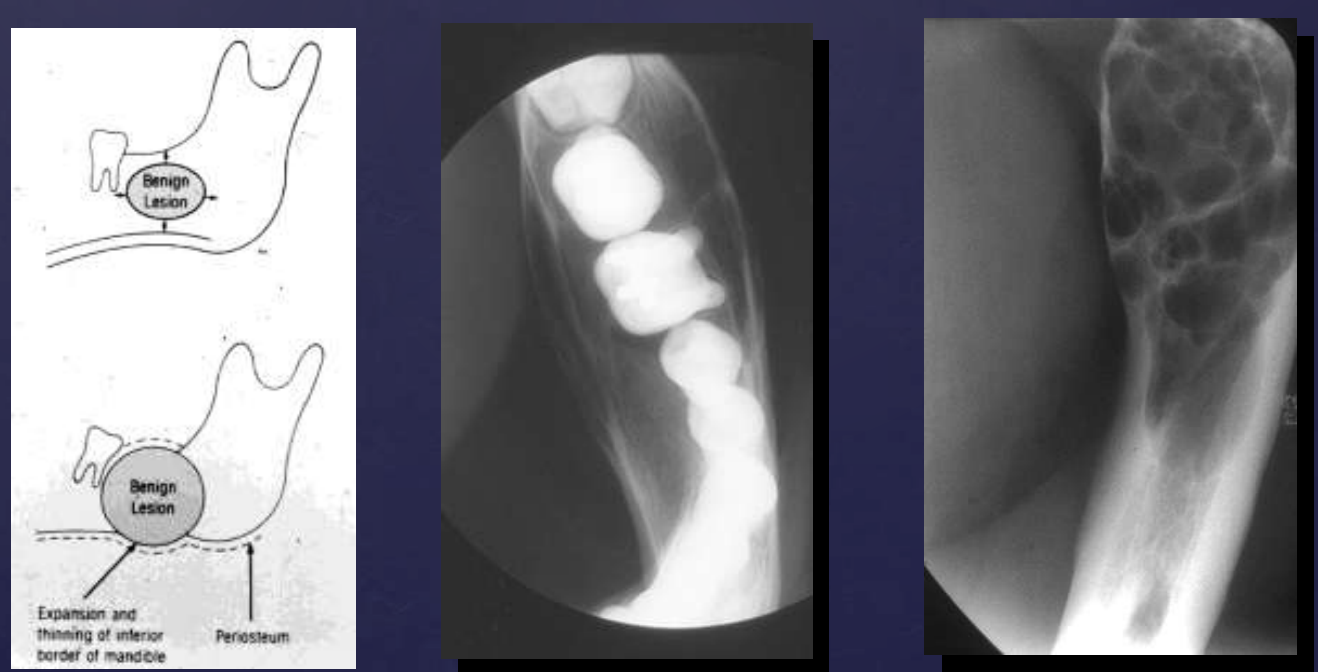

how do benign tumors effect surrounding structures: cortical bone?

expansion

thinning

erosion (in case of aggressive benign lesions)

cortical bone (expansion, thinning, erosion)